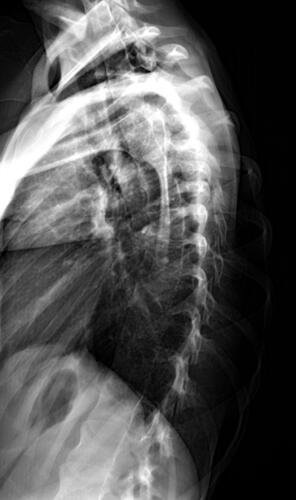

A Vá tem 13 anos e precisa urgentemente realizar uma cirurgia na coluna.Valentina foi surpreendida com o diagnóstico de escoliose hepática grave com 67 graus de desvio (desvio longitudinal da coluna), e precisa realizar com urgência a cirurgia corretiva, os exames foram realizados em Porto Alegre, mas a cirurgia está marcada para dia 13/07 em São Paulo devido a gravidade do caso, para isso a família terá que ficar residindo próximo ao hospital em São Paulo por no mínimo 30 dias para uma plena recuperação. Sabemos bem que qualquer procedimento cirúrgico é delicado, na coluna então nem se fala.Após o diagnóstico e o prognostico dessa doença a família se desfez de alguns bens (carro e moto) para cumprir os prazos dos exames e consultas, necessitando agora arrecadar o valor para a estadia da pequena Valentina e seu pós operatório (medicação, consultas e fisioterapia).

Em anexo os exames (laudo e imagens) para expressas a gravidade do caso.